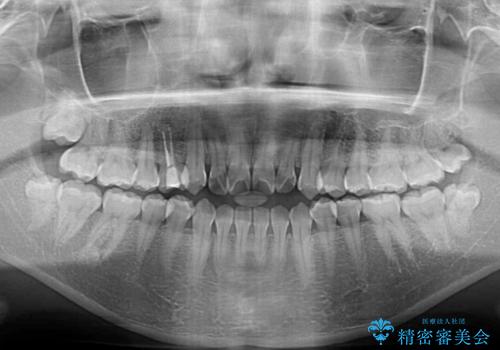

- 上下前歯の隙間を気にして来院された患者様です。

前歯が、舌の突出癖により上下前歯が非接触となっている状態でした。

上下前歯が非接触である開咬は、インビザラインによる治療がお勧めではありますが、しっかりと使う自信がないとのことで、ワイヤー装置にて治療を行うこととしました。

ワイヤー矯正での開咬改善には時間がかかります。

舌の突出癖改善のトレーニングをしっかりと行っていただき、上下前歯が接触する咬み合わせを達成することができました。